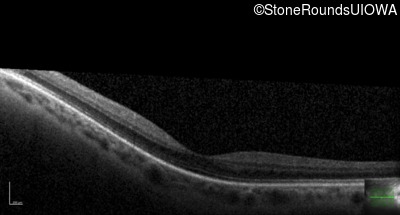

Optical Coherence Tomography - Right - 20/30 +2

Exemplar / OCT Stack